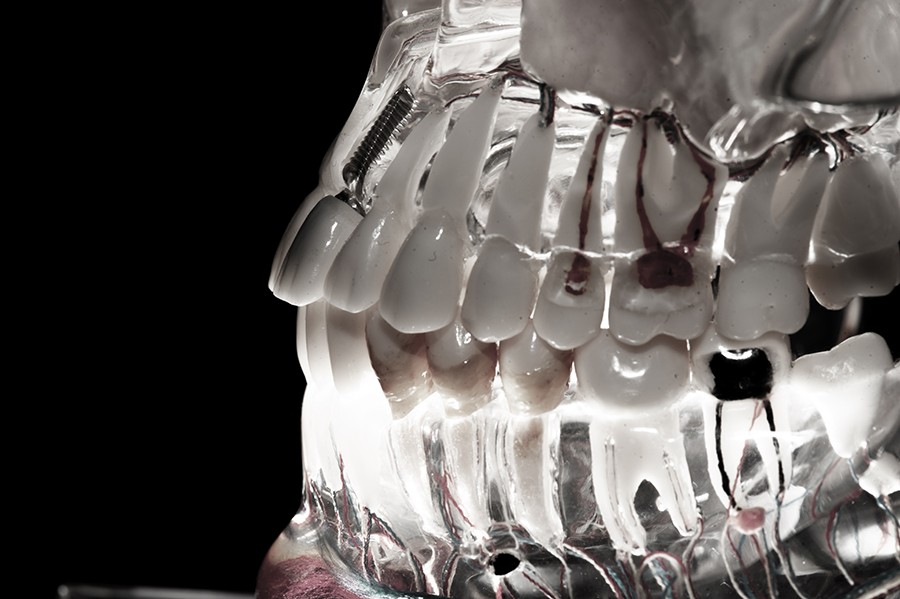

Mikroskop stomatologiczny, czyli operacyjny wykorzystywany w stomatologii – umożliwia odnalezienie kanałów korzeniowych, pozwala zajrzeć do ich wnętrza, ocenić ich rozmiar i kształt. Istotny w ocenie ewentualnych uszkodzeń ścian korzenia, przydatny szczególnie w obszarach trudno dostępnych dla endodonty, jak wielokorzeniowe zęby boczne.

Lupy to niewielkie i wygodne w użyciu przyrządy pozwalające stomatologom oraz endodontom na precyzyjną pracę okiem uzbrojonym.

Zestawy ręcznych oraz maszynowych poszerzaczy kanałowych, mikrosilnik X-Smart o optymalnych zakresach kontroli momentu obrotowego do pracy w kanałach korzeniowych zębów, precyzyjne końcówki do opracowywania kanałów przy użyciu aparatury ultradźwiękowej. Oprzyrządowanie do uplastyczniania i wypełniania kanałów materiałem termoplastycznym. System do plastyfikacji gutaperki, stosowany w metodzie kondensacji bocznej, SUPERENDO BETA

PRZYRZĄDY OPTYCZNE